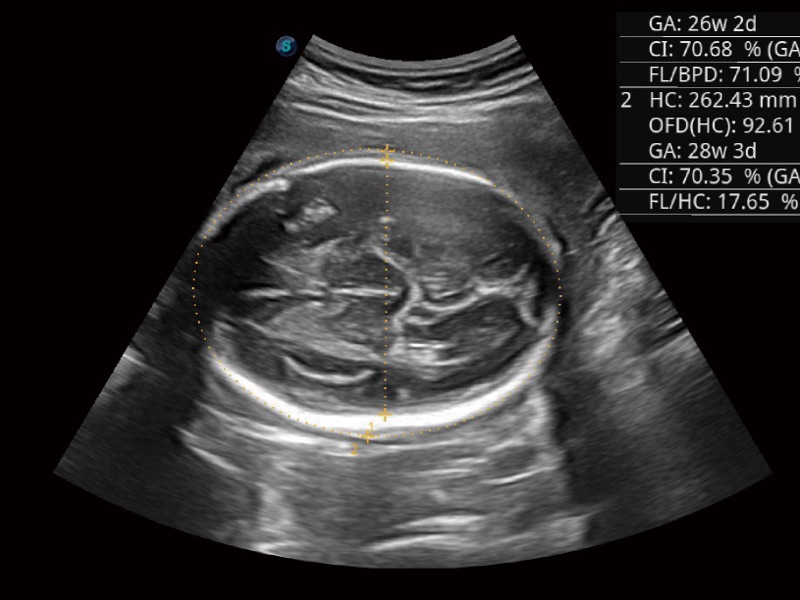

• 妇产科应用